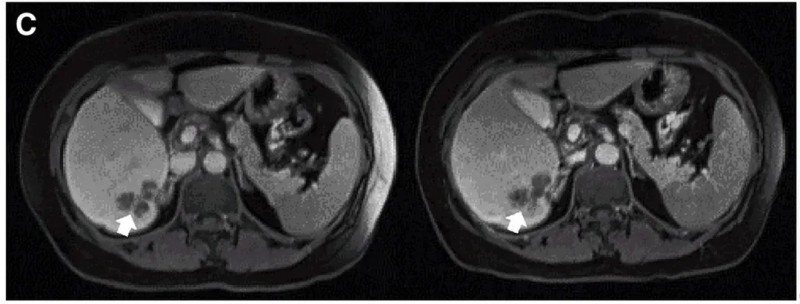

值得一提的是,典型病例P10在接受DL4剂量CEA CAR-T治疗后,MRI检查证实肝内一处病灶明显缩小(详见下图)。

▼P10患者在CAR-T治疗前(左图)、治疗4周后(右图)的MRI对比

▲图源“Molecular Therapy”,版权归原作者所有,如无意中侵犯了知识产权,请联系我们删除